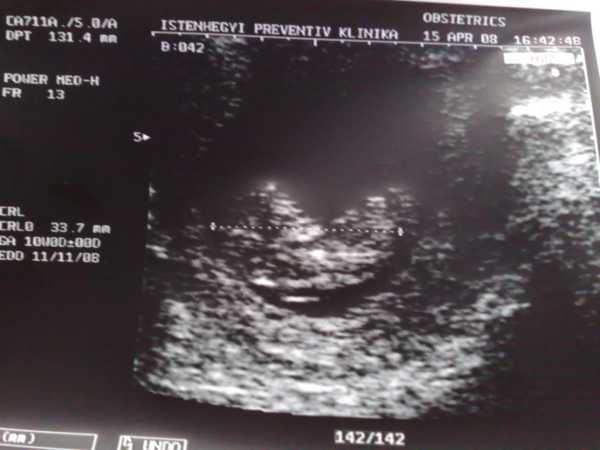

Ime pici bébibogyónk: Kép

33mm és jól van.

Következő UH 05.06[/img]